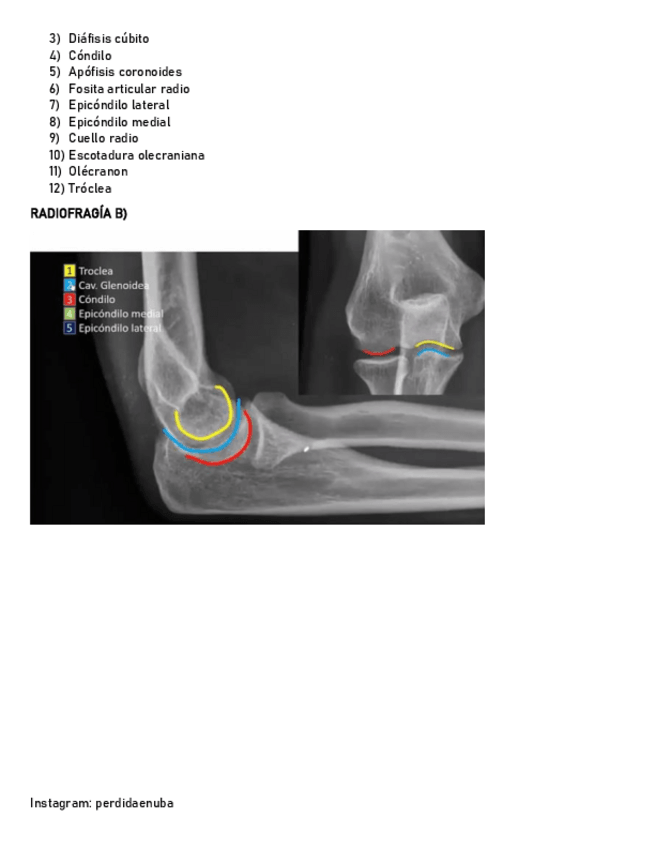

He publicado nuevos apuntes de 8º Cirugía General: BRAZO-CODO-ANTEBRAZO-.pdf